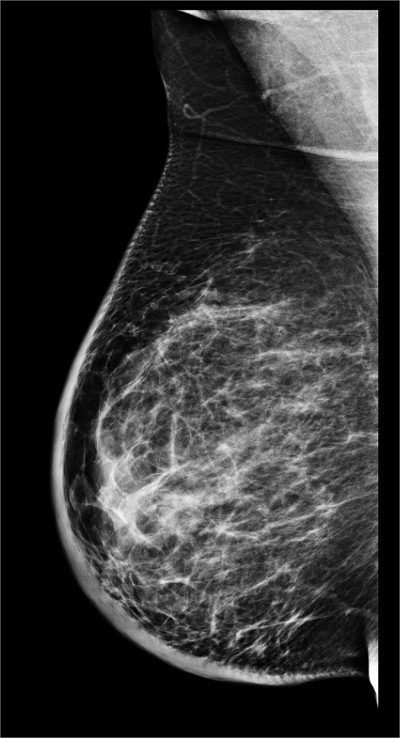

👉In addition to MRI and molecular imaging, both tomosynthesis and breast ultrasound are additional techniques for enhanced screening in patients with dense breasts.

👉Multiple studies have now shown significant benefits from the addition of tomosynthesis to conventional digital mammography alone in screening programs.

👉A prospective multicenter study compared tomosynthesis with bilateral physician hand-held ultrasound screening in 3231 asymptomatic patients with mammography-negative dense breasts.

– In all, 24 additional cancers were detected, 23 of which were invasive.

– Tomosynthesis detected 13 cancers, and ultrasound detected 23.

– These data suggest that even though tomosysthesis significantly increases the number of cancers found in dense breasts, in the hands of a skilled breast radiologist, ultrasound may be even better.